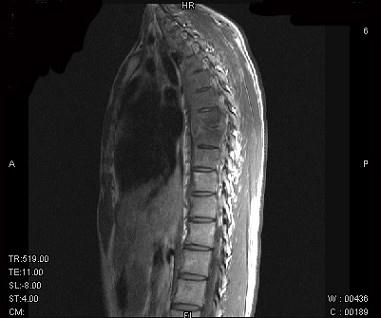

问题 男,21岁,有午后发热,夜间盗汗等,胸部疼痛,活动时加重,休息后减轻,请结合所提供图像,选择最佳答案 ( )

选项 A、骨巨细胞瘤 B、胸椎结核 C、胸椎骨转移 D、胸椎退行性变 E、骨髓瘤

答案 B